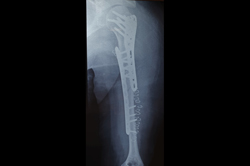

Subtrochanteric Fracture